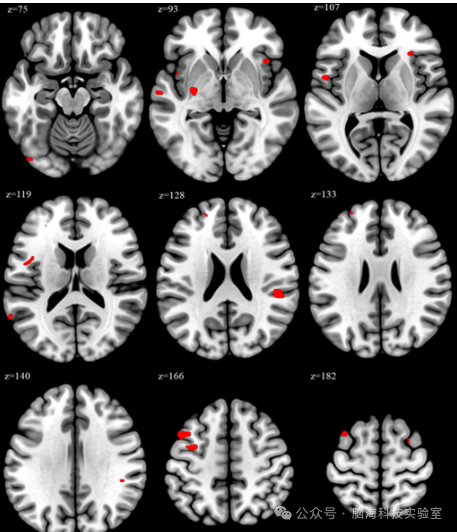

基于体素的形态测量(VBM)分析结果图

图中展示的是VBM分析的结果,其中红色区域标示了在过度劳累组中灰质体积显著增加的大脑区域。这些红色区域在统计上显示出与非过度劳累组相比具有显著性差异(p<0.05,经过家族错误率(family-wise error, FWE)校正),这意味着这些区域的灰质体积增加不太可能是由随机变化引起的。

图中的每个切片都对应大脑的一个特定Z坐标,这是在标准空间中的位置,用于确保不同个体的大脑图像可以准确对齐和比较。结果图表明,与非过度工作组相比,过度工作组在17个区域的VBM峰值显著更高(p<0.05FWE校正)。这些区域包括左中额回、左中央前回、左中央盖、双侧上额回(背外侧)、右上颞回和左岛叶皮层。在过度工作组内进行的Spearman相关性分析显示,每周工作小时数与左中额回、左中央前回、左中央盖、左上额回、右上颞回和左岛叶皮层的VBM峰值之间存在显著正相关。这些发现表明,增加的工作量与与执行功能和情绪调节相关的脑区体积变化之间可能存在潜在关系。